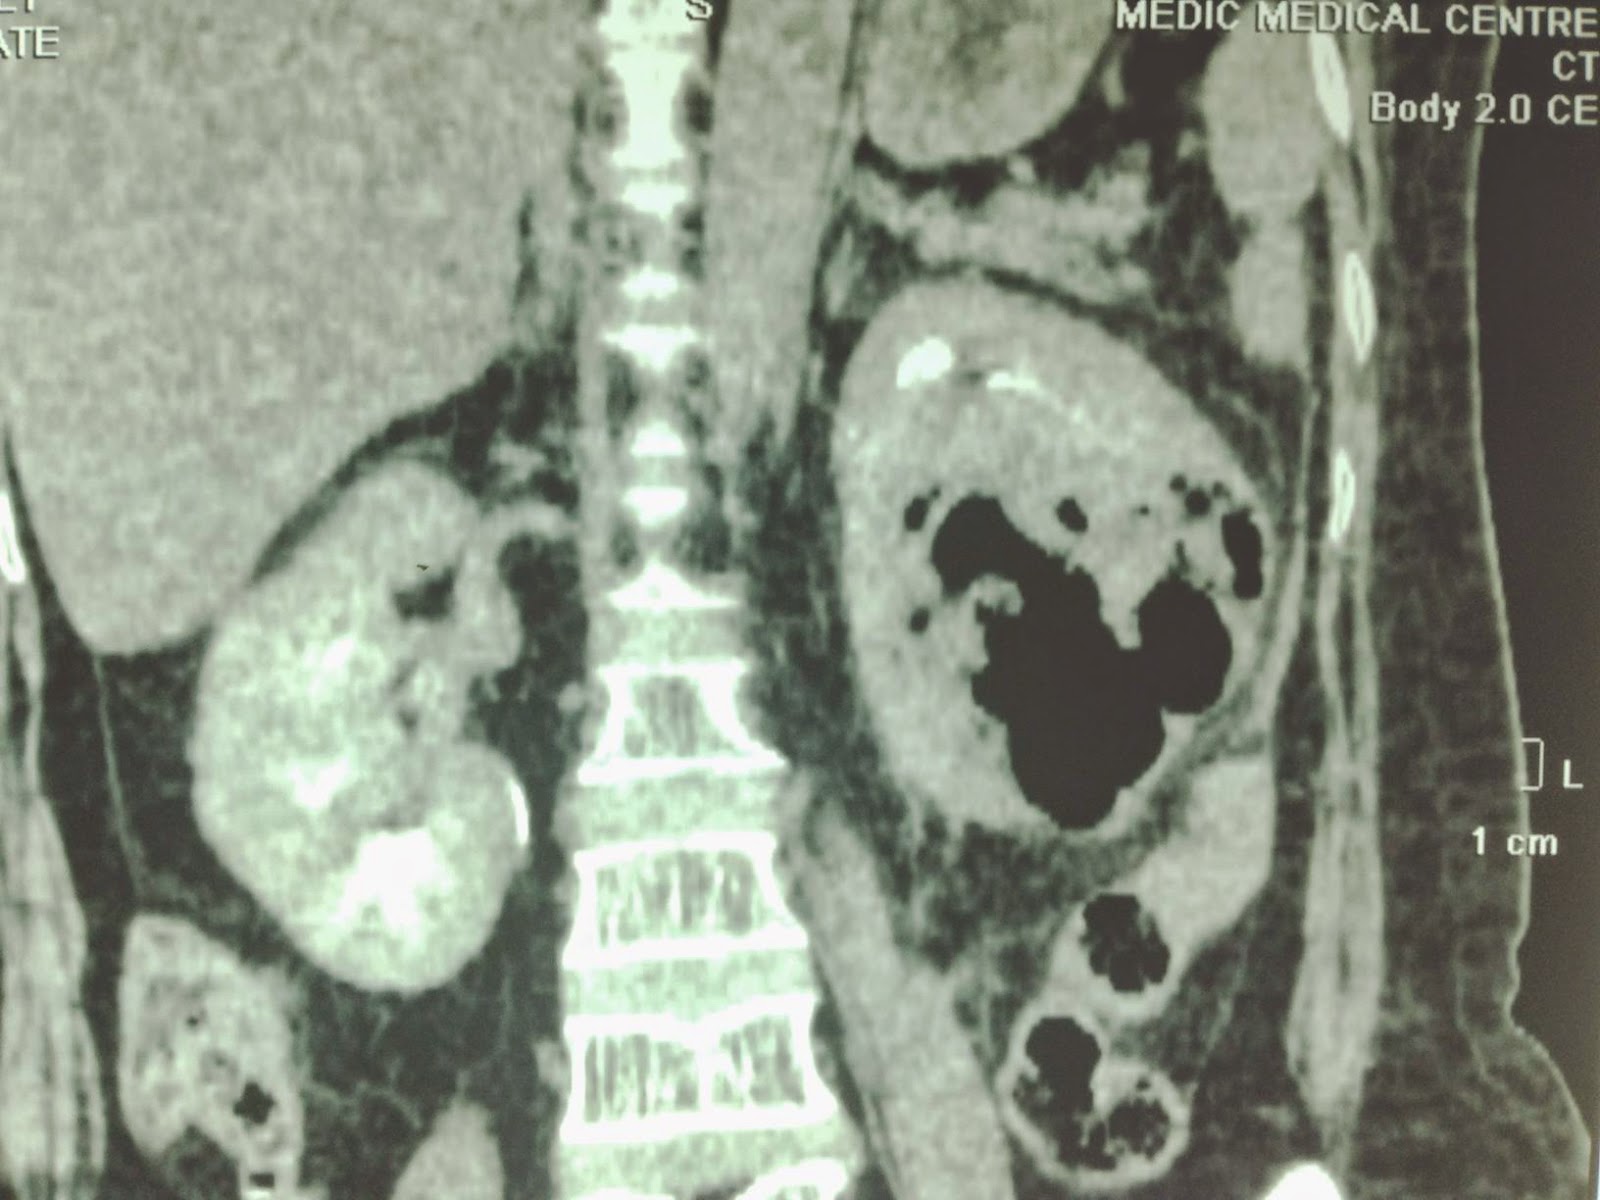

(a) Renal CT scan showing an abscess in the left kidney (blue arrow Abscess Kidney It may cause fever, flank pain,. a kidney infection (pyelonephritis) is a serious bacterial infection that can cause fever, pain and kidney damage. a renal abscess is a pocket of infection in the kidney that can cause fever, pain, and kidney damage. renal abscess is a collection of infective fluid in the kidney. renal and perinephric. Abscess Kidney.

Abscess Lower Pole Right Kidney Kidney Case Studies CTisus CT Scanning Abscess Kidney a kidney infection (pyelonephritis) is a serious bacterial infection that can cause fever, pain and kidney damage. a renal abscess is a pocket of infection in the kidney that can cause fever, pain, and kidney damage. It is usually a sequela of acute pyelonephritis, where severe vasospasm and. renal and perinephric abscesses are rare but very severe. Abscess Kidney.